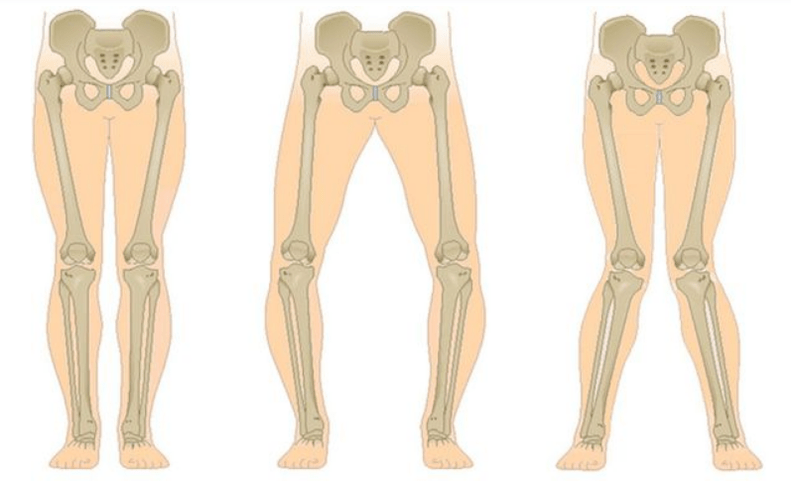

Το τελευταίο στάδιο της γονάρθρωσης διακρίνεται από το γεγονός ότι ο πόνος γίνεται σχεδόν σταθερός, προκαλώντας άγχος όχι μόνο κατά το περπάτημα, αλλά και κατά την ανάπαυση, ακόμη και τη νύχτα, όταν οι ασθενείς πρέπει να αναζητήσουν μια άνετη θέση για ύπνο. Η κίνηση είναι πιο περιορισμένη: είναι δύσκολο να λυγίσεις και να ισιώσεις τελείως το πόδι. Η άρθρωση παραμορφώνεται και αυξάνεται σε όγκο. Συχνά παρατηρείται παραμόρφωση Valgus (σχήματος X) ή varus (σε σχήμα Ο) των ποδιών. Το βάδισμα γίνεται ασταθές και κουνιέται. Σε σοβαρές περιπτώσεις χρειάζεται μπαστούνι ή πατερίτσες.

Ανάλογα με τον αριθμό των προσβεβλημένων αρθρώσεων, διακρίνεται η μονόπλευρη και η αμφοτερόπλευρη γονάρθρωση.